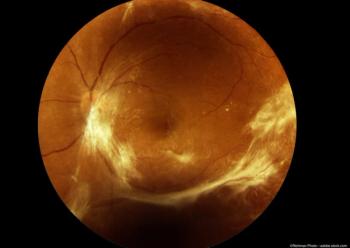

The study will evaluate the safety and efficacy of fluocinolone acetonide intravitreal implant 0.18mg, (YUTIQ) in the treatment of chronic non-infectious uveitis and related intraocular inflammation.